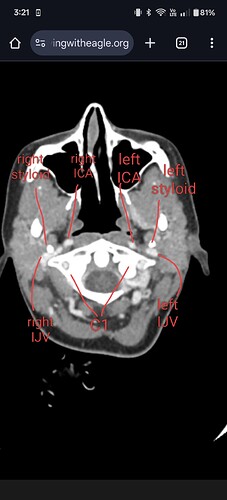

@Happyface12e perfect. See attached annotated image.

Your right IJV (left side of image) is pretty compressed between your right styloid and C1. Your left styloid is also touching your left IJV but not nearly as severely as your right side.

Additionally, your right IJV is your dominant (bigger) IJV. Major compression to the dominant IJV can significantly contribute to intracranial hypertension symptoms since the biggest mover of blood out of the brain is compressed.

Although I think you could benefit from bilateral styloidectomy, your right side should be of top focus. That is, unless the tip of your left styloid is compressing an artery or something which could take precedence over IJV compression. But assuming that isn’t happening, you definitely should see about getting that right styloid dealt with and specifically, cut above the level of C1. Don’t get a styloidectomy unless the surgeon specifically is able to cut the styloid above the level of C1 or you’ll wake up and still suffer from IJV compression.